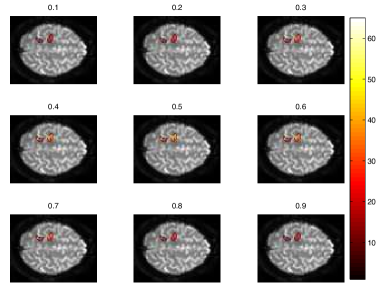

We first qualitatively inspected the predictions made by the GP and its ability to extract a continuous profile of AD image phenotypes. Figure 3 shows a set of example traces collected from various locations of the brain. The asterisks in the figure show the observed voxel-specific z-scores at their respective MMSE scores. Also shown are the predicted posterior mean activation profile and the predicted posterior variance of the activation profile. The profiles show varying degrees of variability depending on brain region the profile. Some profiles appear to show several peaks along the MMSE axis while others show a delayed and gradual increase at the higher end of the MMSE spectrum. Looking at the spatial distribution of predictions, Figure 4 shows the changes predicted activation in the temporal lobe with equidistant increases in MMSE scores, starting with MMSE value of 202020 at top and finishing with MMSE value of 303030 in the bottom row of the figure. Figure 4a shows the predicted mean activation while figure 4b shows the predicted variance in the activation. Clearly visible is the increase in activation spread and intensity. Also very clearly visible is an intermediate increase in variance at MMSE (444th and 555th image row). These images correspond to images at MMSE values that are not contained in the data set. Also, there is a tendency of the variance to decrease with increasing MMSE. This effect is primarily due to the increased quality of the images as patients become more similar to control subjects (MMSE=303030).

Refer to caption

(a) The predictive mean

(b) The predictive variance

Figure 4: Changes in temporal lobe activation with improving MMSE. Left: Predicted mean activation; Right: Predicted activation variance.